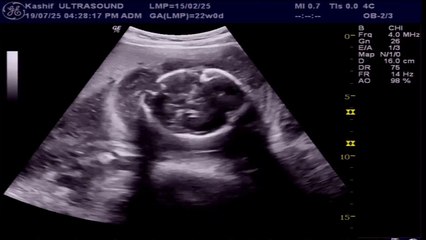

Amniocentesis (also referred to as amniotic fluid test or AFT), is a medical procedure used in prenatal diagnosis of chromosomal abnormalities and fetal infections.